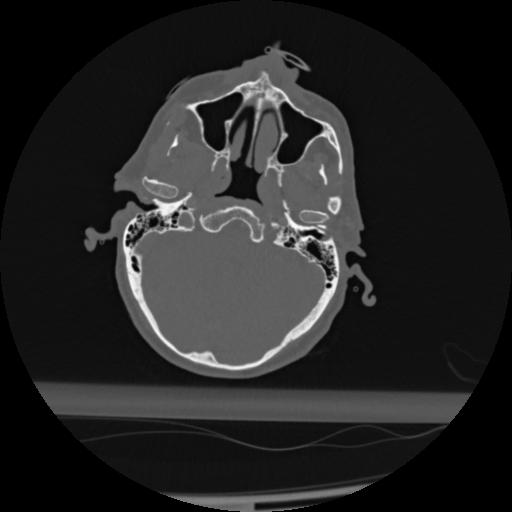

22 ANGIO,CE,Vol,0.5,ANGIO,,